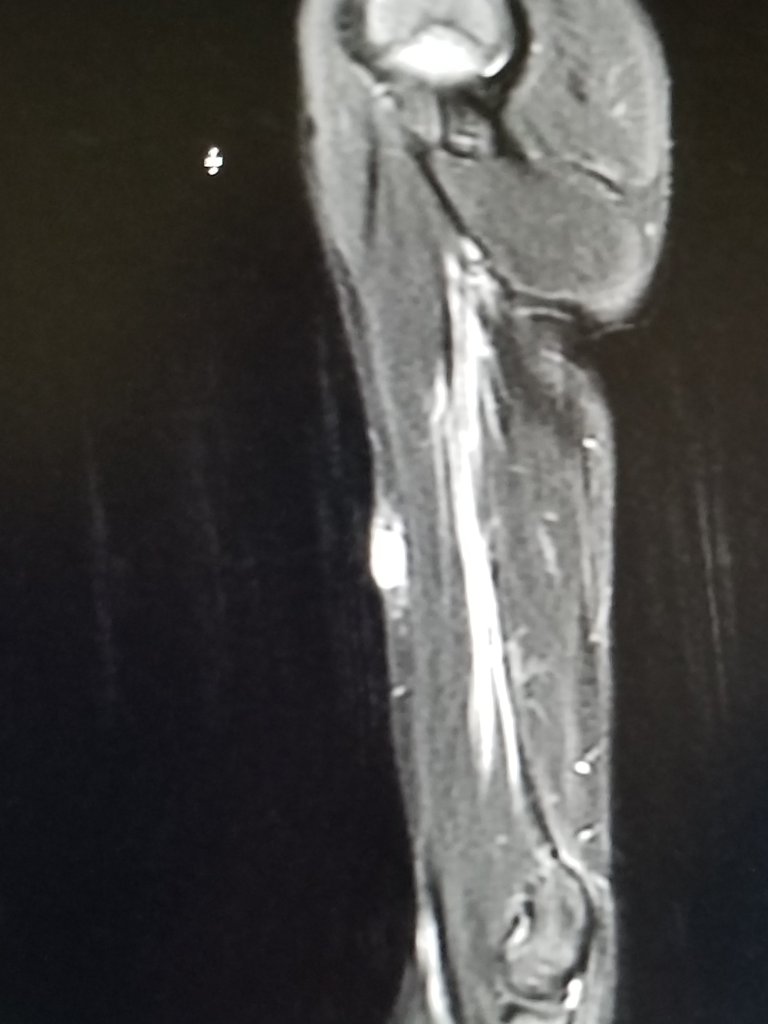

The radiologist reports were ready to download when we got home. While, the MRI isn’t definitive, by itself, it indicates possible recurrent disease in Eli’s left foot and thigh and right upper arm. The PET/CT will help confirm the recurrence and then discuss with the doctors what the next step will be.